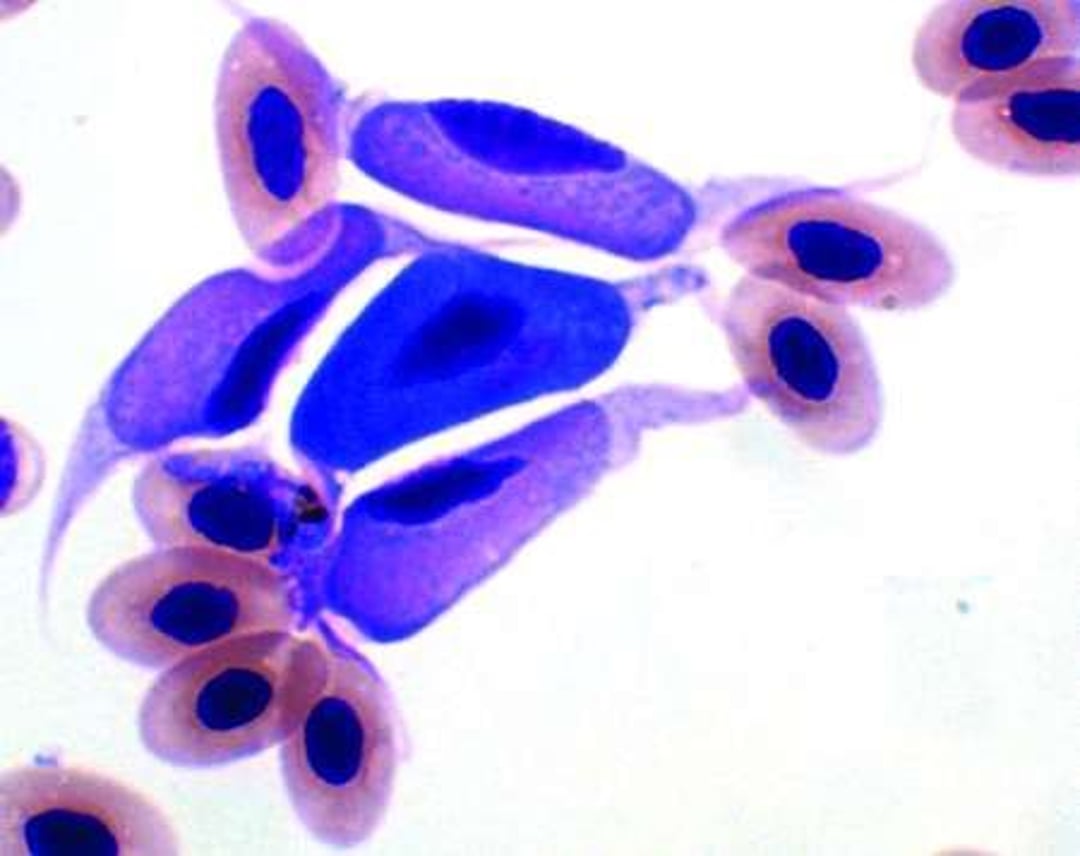

Leucocytozoon, photomicrograph, blood, red-tailed hawk

Photomicrograph showing Leucocytozoon gametocytes in a blood smear from a red-tailed hawk (Buteo jamaicensis). Gametocytes fill the host cell cytoplasm and displace the nucleus laterally. Note the dark blue staining of the macrogamont in the center, and the lighter pink staining of the three microgamonts surrounding it. Giemsa stain; original magnification 1,000X.

Courtesy of Dr. H. J. Barnes.